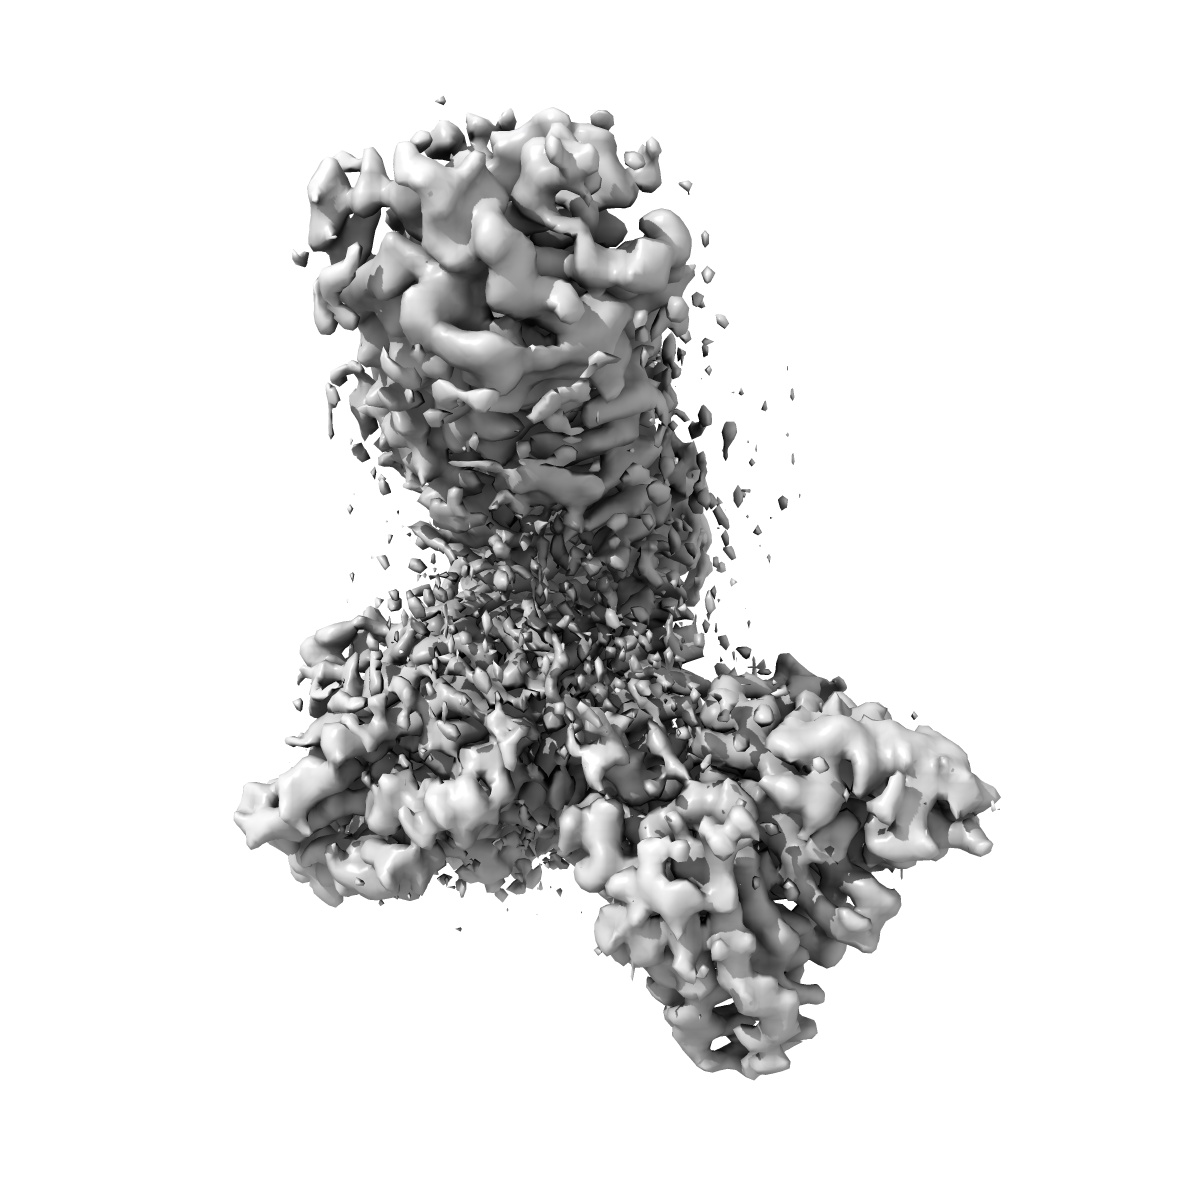

Cryo-EM structure of the 9-hydroxystearic acid bound GPR120-Gi complex

Single-particle3.1 Å

Sample: Cryo-EM structure of the 9-hydroxystearic acid bound GPR120-Gi complex

Unsaturated bond recognition leads to biased signal in a fatty acid receptor.

(2023) Science , 380 , eadd6220 - eadd6220